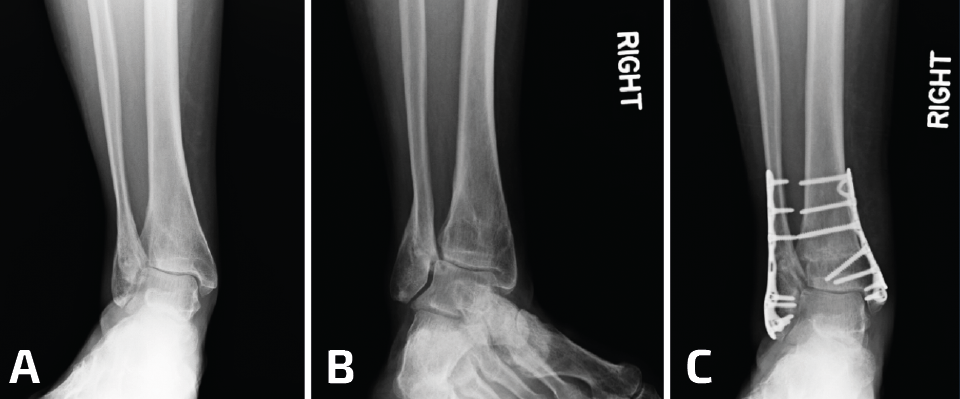

Otra variante de una consolidación viciosa del peroné se asocia con la compresión del pilón externo y la inclinación en valgo de la mortaja del tobillo. Como se describió más arriba, estos casos deben tratarse mediante osteotomía del peroné, además de una osteotomía en cuña de sustracción de la cara interna de la tibia para la realineación del tobillo (Figuras 8 y 9).

Figura 9. Las consolidaciones viciosas o pseudoartrosis del peroné pueden producirse en el contexto de una fractura de estrés. En este paciente, una fractura por estrés tras una triple artrodesis indica una deformidad en valgo (A, B). A pesar de elongar 1 cm el peroné, se debe realizar una osteotomía de cierre lateral de la tibia distal (C, D).

Otra opción consiste en realizar una osteotomía en cuña de adición de la cara externa de la tibia distal (plafonplastia) para lograr una posición plantígrada del tobillo. Por lo general, esta deformidad es el resultado de una lesión por aplastamiento del tobillo y el pilón externo, e independientemente de la realineación y fijación del peroné, si el pilón externo permanece con hundimiento, recurrirá la deformidad en valgo y la artrosis (Figura 7)(12,13).